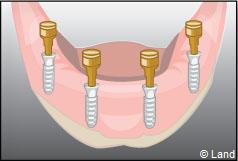

Exemple d’une réhabilitation complète implantaire

Situation clinique terminée

Les implants peuvent aussi servir à stabiliser un appareil amovible au maxillaire supérieur comme au maxillaire inférieur. Dans ce cas, les implants retiennent la prothèse amovible par des systèmes d’attachement.

Deux techniques sont possibles. Elles font appel à la barre de rétention ou aux boutons-pressions.